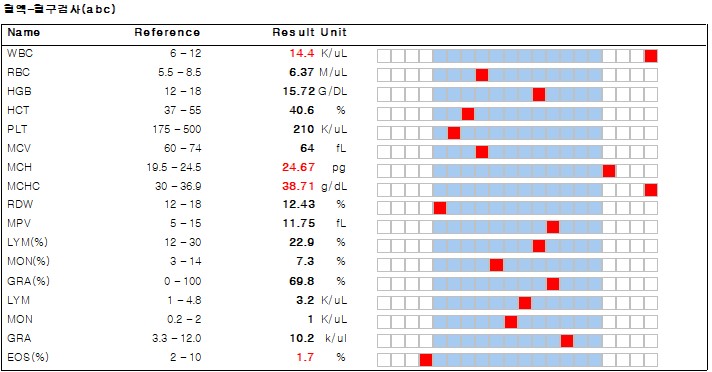

몽*은 설사와 식욕 부진으로 강서구 까치산역 세인트동물병원에 내원하였습니다.기초적인 문진 후 혈액검사를 실시했습니다.

혈액 검사에서는 염증 수치가 상승한 것 이외에는 별다른 소견이 없었습니다.